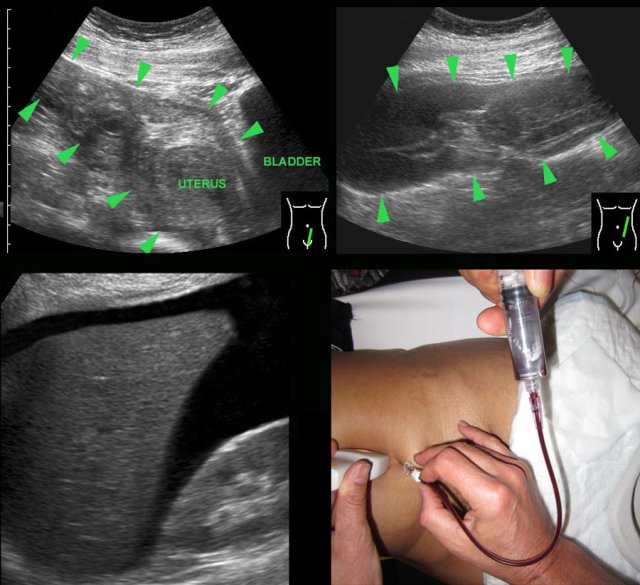

case 2

In this patient submitted for suspected stomach perforation, a large inhomogeneous mass of blood clot (arrowheads) in the left peritoneal cavity was visualized (right upper image).

Such a

large clot can easily be mistaken for normal mesenterial fat or bowel.

Awareness

and careful inspection of this mass, which lacks peristaltic movements, are helpful findings to differentiate.

This patient had also a lot of free fluid, which at puncture was liquified blood (right lower image).

Laparoscopy demonstrated 1.5 liter of blood and a ruptured tubal pregnancy.